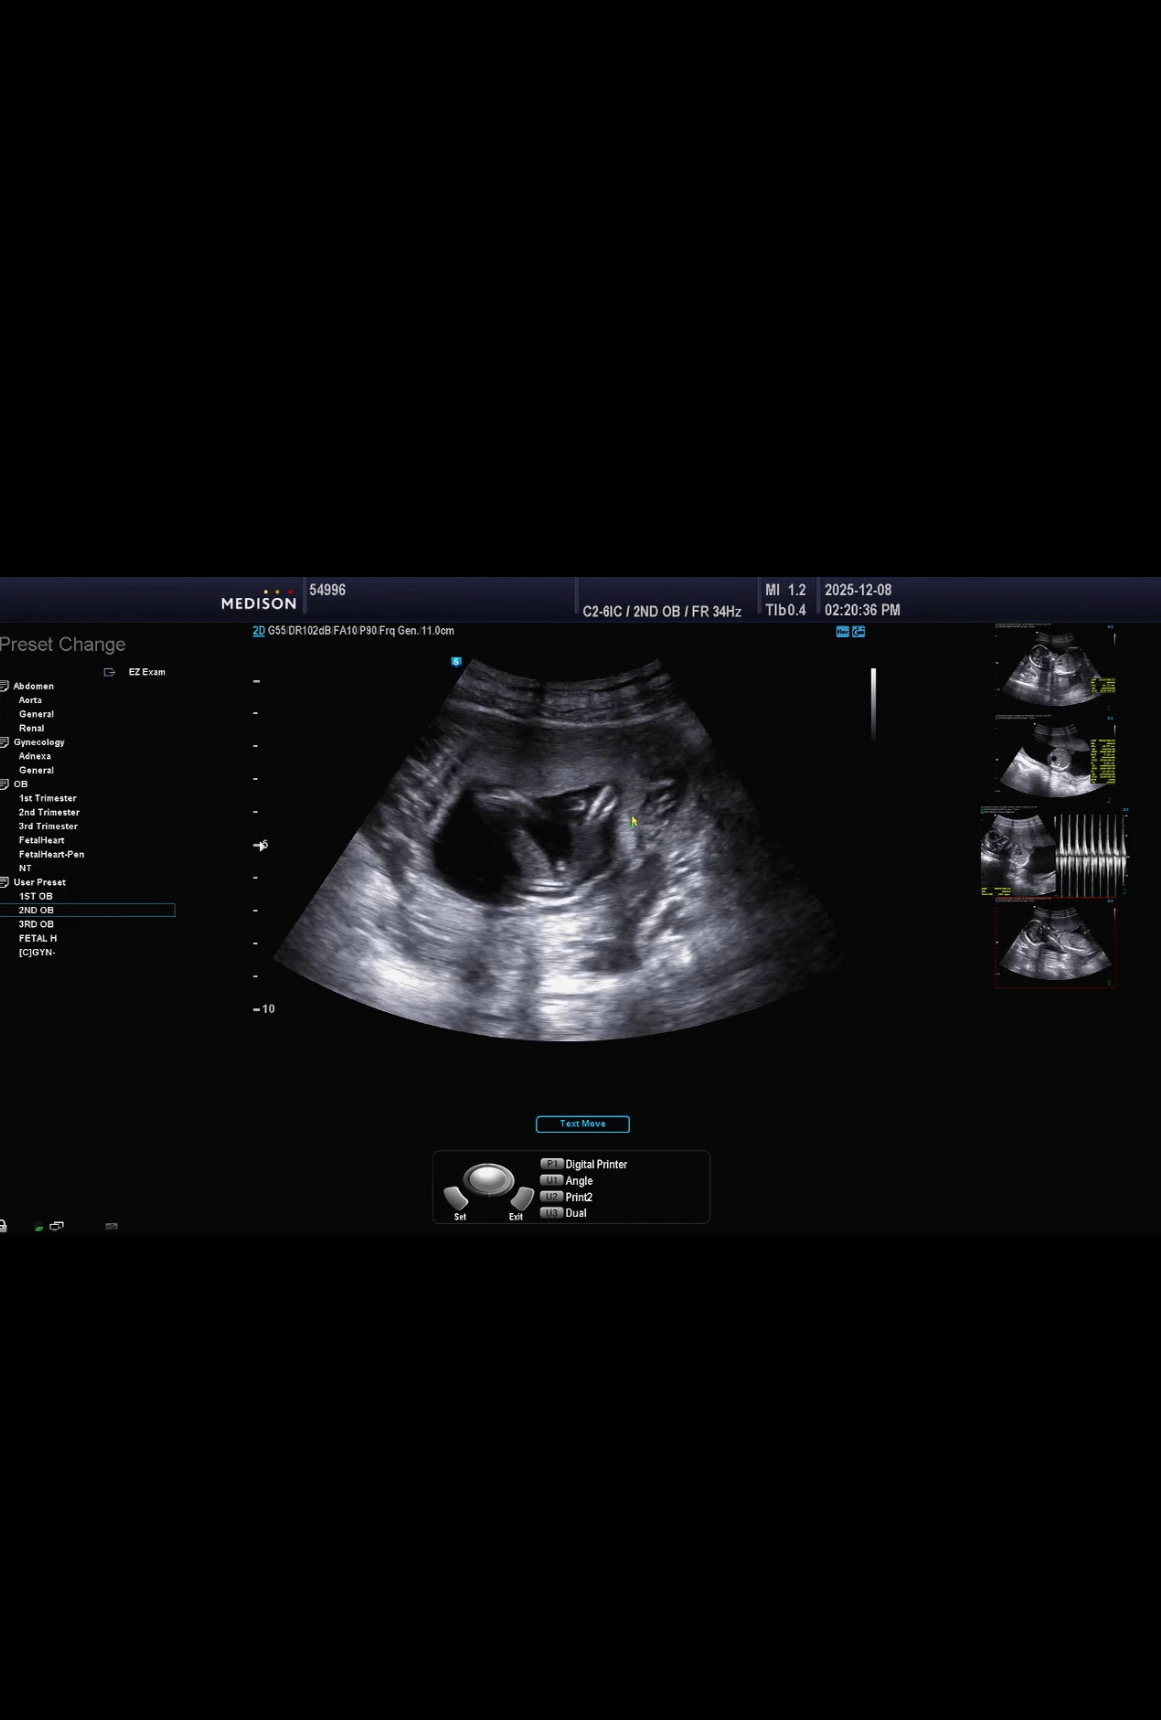

이번주에 시댁에서 젠더리빌 하기로 했는데 16주 검진받고 혼돈이에요 ,, 분만병원에서는 원래24주에 알려준다고 하시면서 아들일 확률이 높다고 초음파 보여주셨어요 그러나 확신 못합니다 라고 말씀하셔서 애매했어요 저도 가랑이 사이로 뭔가 튀어나온 걸 봣거든요? 🤔 근데 더 확실히 알고싶어서 서브병원가서 바로 다음날 보고왔는데 아기가 보기 어려운 자세로 있어서 좀 애먹으면서 봤어요 근데 여기 선생님께서는 90프로는 딸일거라고 가랑이가 매끈하다고 하시더라고요 틀린적은 한 번도 없지만 다른 날 또 와서 한 번 더 보라고 하셨어요 저 젠더리빌 떡주문하기 직전인데 그냥 느낌으로 가야할까요? 🤪 사진이 한장만 올라가네요 분만병원 초음파 가랑이사진이고요 서브병원사진은 또 가랑이가 민둥해요 🧐

올려주신 사진으로는 ㅋㅋ빼박 아들인뎅!!!!

그쵸,,근데 서브병원 사진은 아무것도 없어서,, 거의 8분을 봐주셨는데 또 그 분은 90프로 딸 일 것 같다고 해서 혼란스러워요?! 🤪

제가 초음파사진상으로 볼땐 아들같은데요..

서브병원 사진은 또 완전 민둥산이어요 ,, ㅜ